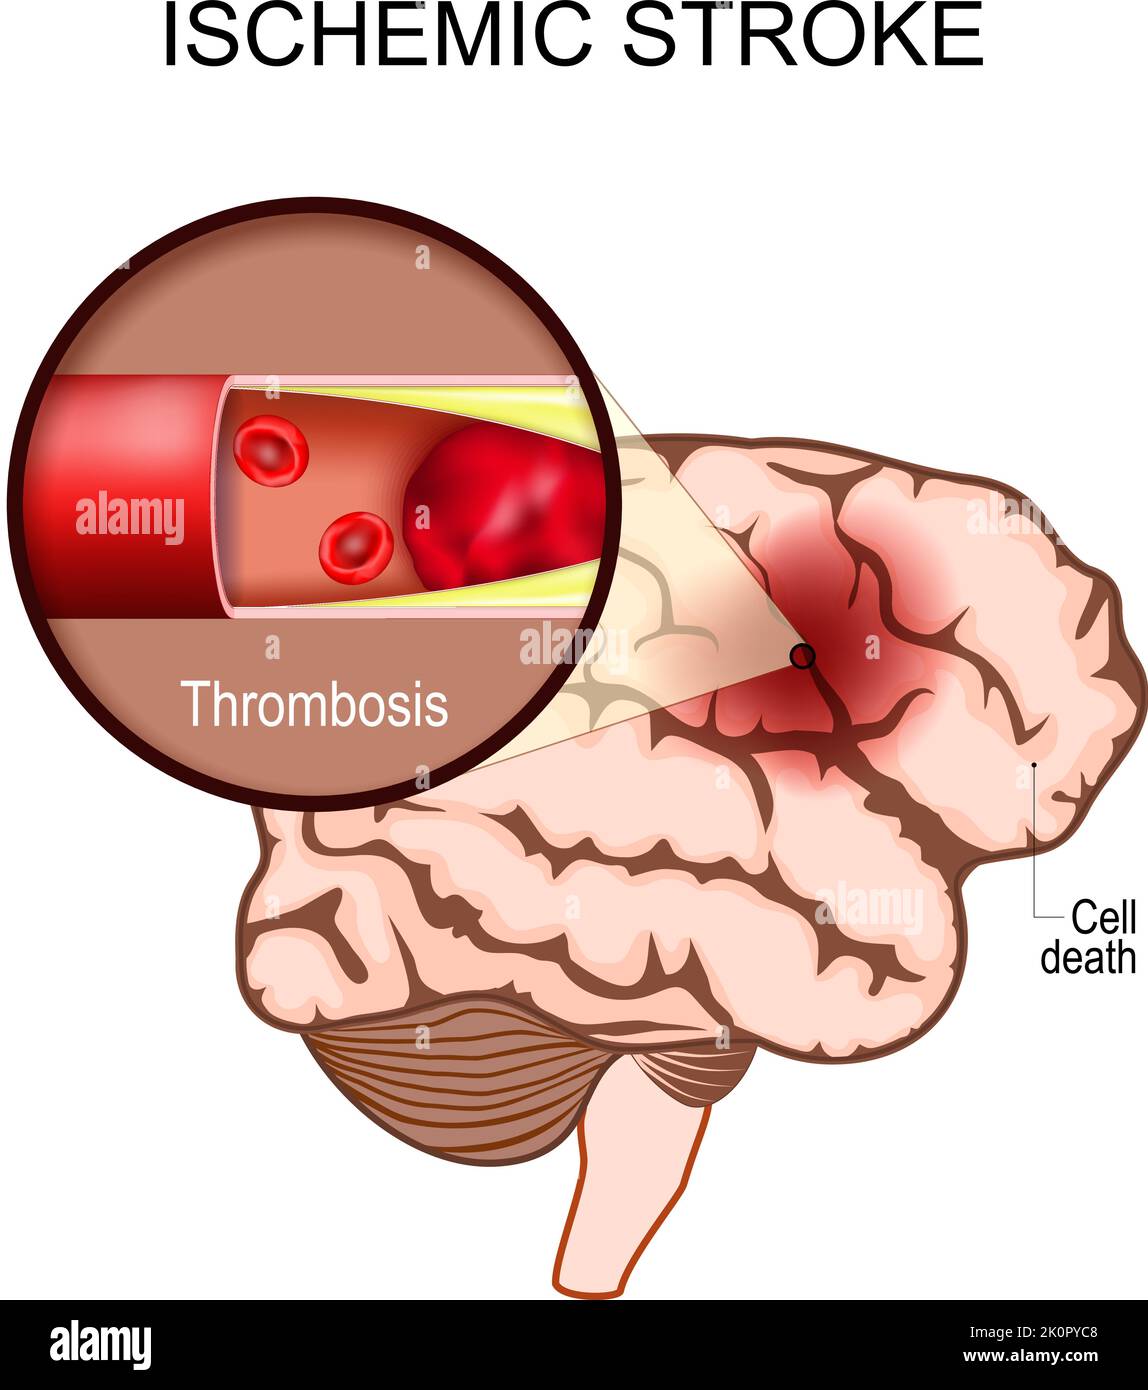

RF2K0PYC8–ictus ischemico. Cervello umano. Primo piano di un coagulo di sangue in un'arteria con conseguente morte cerebrale nell'area interessata. Trombosi. Infarto cerebrale